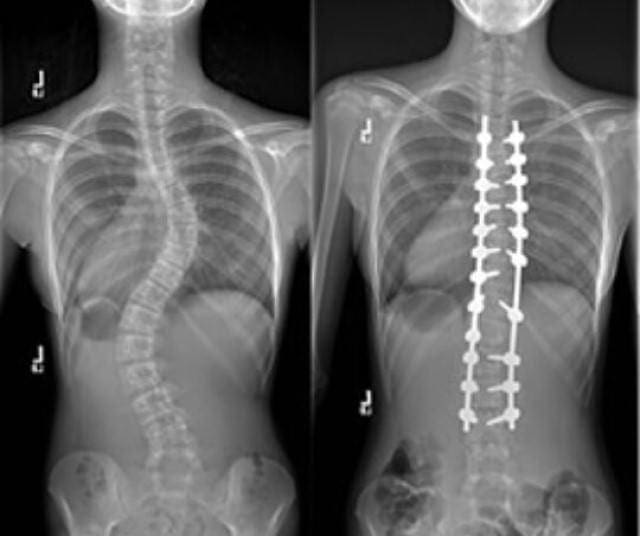

The curve in Lily’s spine didn’t go away when she first discovered it at the age of 12. Her spine continued to worsen, and the curve became more and more noticeable.

Lily even found excuses not to go to physical education lessons, to avoid undressing in front of friends who might notice she was a little different. Perhaps hoping it would just go away, Lily was doing her best to hide the condition from anyone. After her mother spotted how curved in her spine was something had to change.